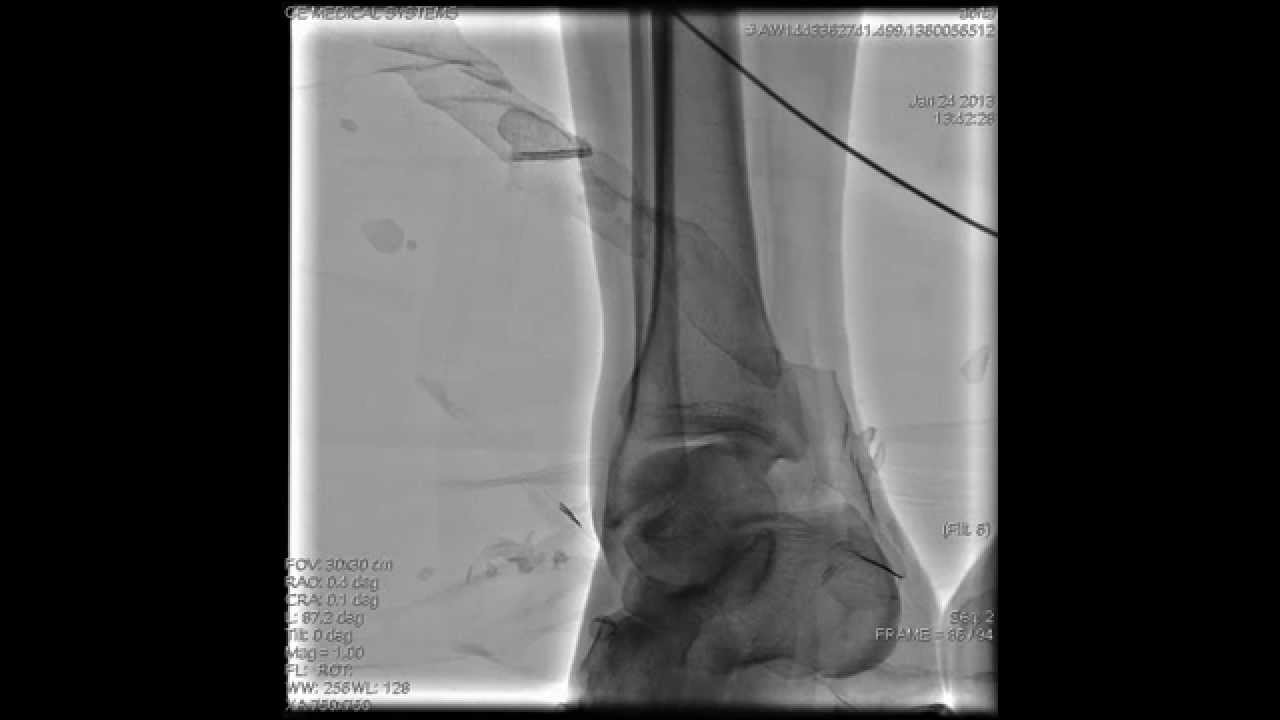

Пациент ложится на специальный стол, который двигается под томографом. С помощью катетера через капельницу вводится в вену контрастное вещество. Когда раствор йода попадет в кровяное русло, стол начинает двигаться под томографом, делая снимки тех областей тела, которые нужно обследовать.

В ходе сканирования кровеносных сосудов ног томографом врач получает на экране монитора снимки сосудов в трехмерном изображении. Какие-либо неприятные ощущения, боль или дискомфорт во время сканирования томографом отсутствуют.

КТ нижних конечностей с контрастом и другие разновидности

МСКТ или КТ ангиография кровеносных сосудов проводится с введением контрастного вещества либо без него. Преимущество отдается ангиографии с использованием контраста. Данный метод позволяет увидеть не только большие и малые сосуды, в том числе и капилляры, но и окружающие мягкие ткани, что способствует более точной и развернутой диагностике заболеваний ног.